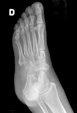

POSICION 1 : PIE AP (DORSOPLANTAR)

Paciente en decubito supino,la rodilla flexionada y con la planta del pie sobre el cassete radiografico.El haz de rayos se dirige verticalmente a la base del primer metatarsiano.

CONSIDERACIONES MEDICAS Posicion 1 : PIE AP

Radiografía en la que se debe tomar en cuenta la totalidad de los elementos, los óseos así como las partes blandas , por lo que es importante recalcar que sean observados , parte del tarso los metatarsianos y sobre todo la orientación de falanges, no es imprescindible el desplegar los sesamoideos ya que estos serán mejor apreciados en enfoques oblicuos y perfiles .También en este enfoque es importante apreciar la congruencia articular del tarso y de los metatarsianos con las falanges , la mesura de los ángulos interdigitales y de las falanges entre si son muy importantes en ortopedia.

Nota jamás conformarse con solo este enfoque , siempre deberá estar acompañado de un perfil , y si es necesario una oblicua . Dr.Aramayo